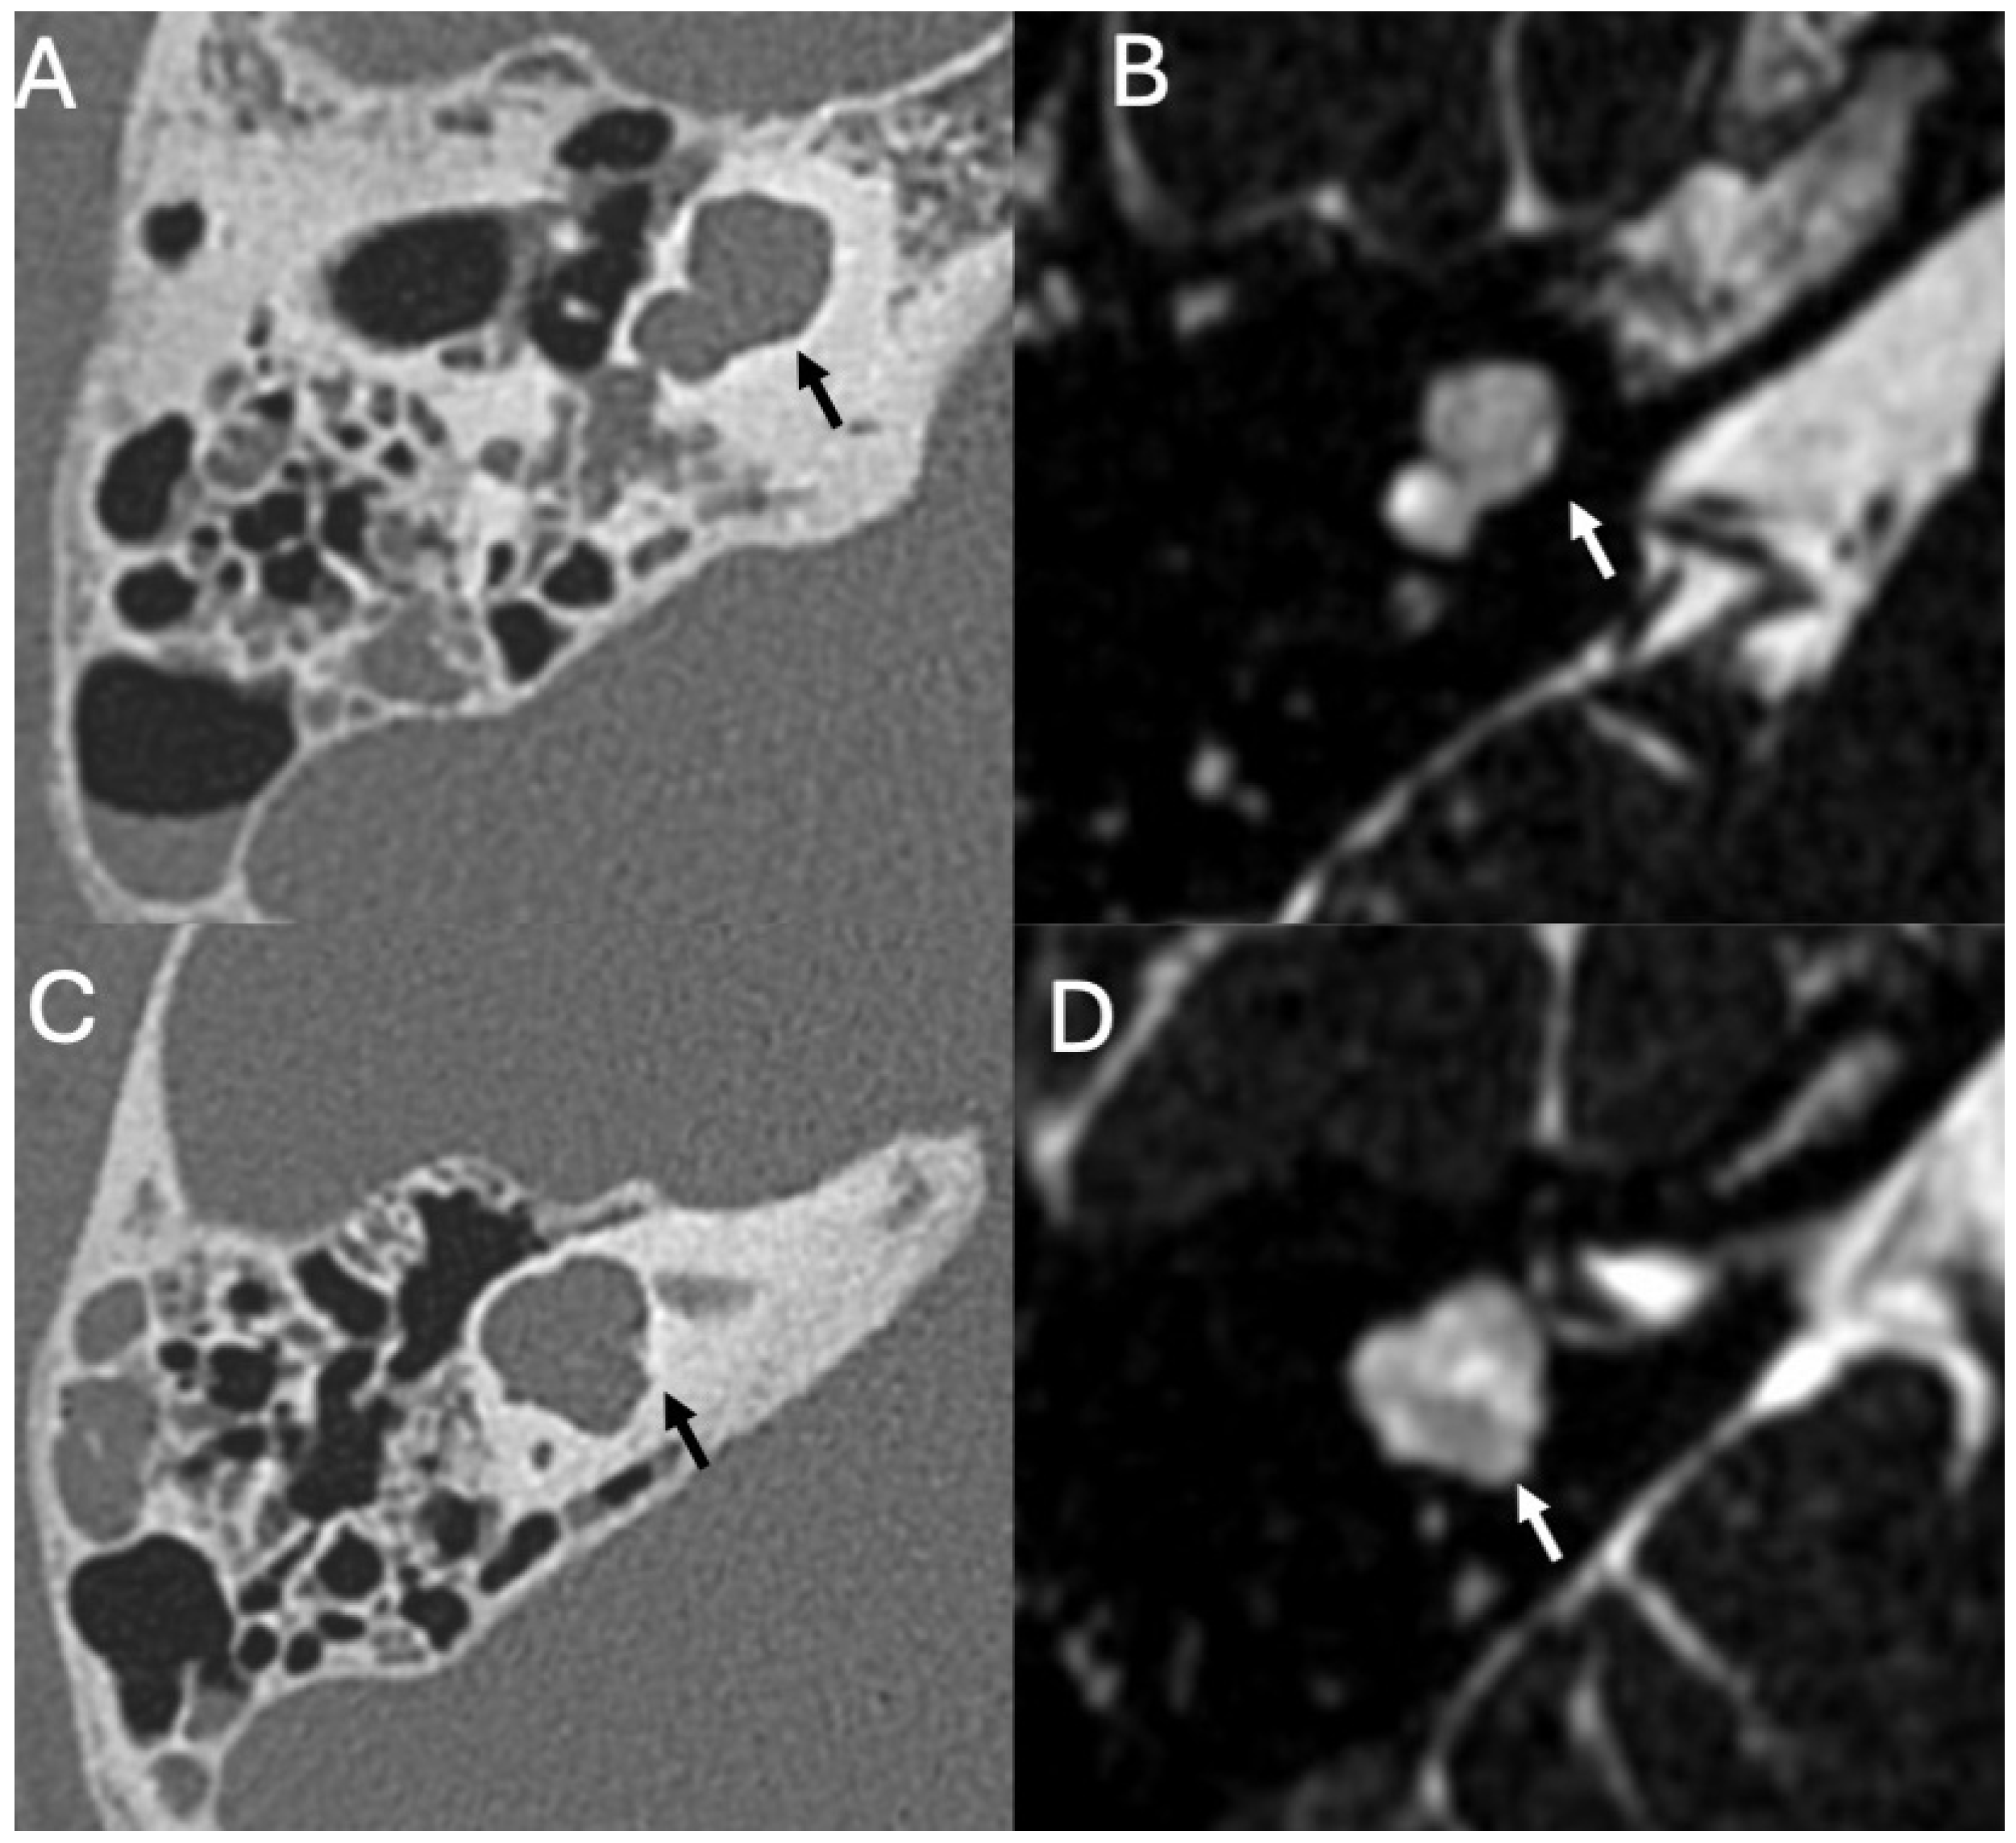

3.3. Cholesteatoma

3.3.1. Imaging

3.3.2. Complications

| Cholesteatoma and Otogenic Complications | Kuo et al., 2015 [26]; Baráth et al., 2011 [27]; Mustafa et al., 2014 [28]; Dubey et al., 2010 [29]; Sun et al., 2014 [30]; Lee et al., 2020 [31] | Reviews and retrospective studies | Cholesteatoma causes erosion and CSF leak, leading to meningitis (12–30% incidence); MRI improves detection; pediatric risk emphasized. |